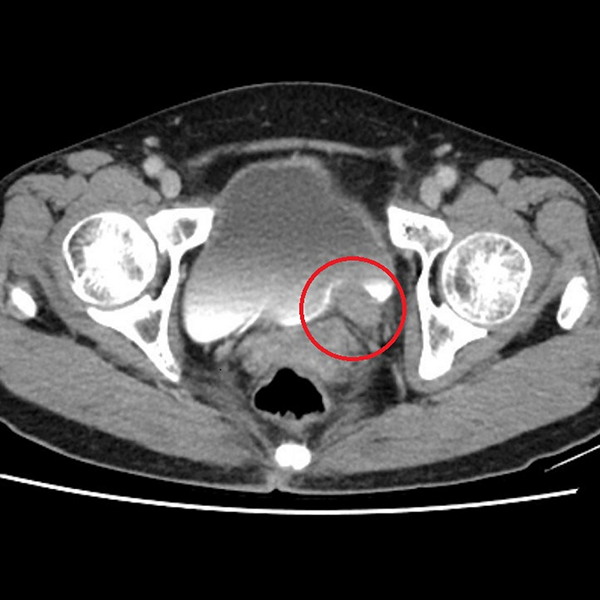

輸尿管是連接腎臟與膀胱的重要管道,負責將腎臟產生的尿液順利輸送到膀胱儲存與排出。根據衛生福利部統計,泌尿上皮癌發生率每十萬人中約有40-50例,臨床上,醫師會以尿液檢驗、膀胱鏡、超音波與電腦斷層進行診斷,排除泌尿道感染、輸尿管結石等會伴隨疼痛的血尿後,就要高度懷疑腫瘤的可能。許竣凱醫師指出:「長期吸菸、處於環境汙染及具家族史者都是危險因子,輸尿管泌尿上皮癌症狀並不明顯,常見表現為無痛性血尿,若置之不理,腫瘤可能造成阻塞及腎衰竭、或是逐漸擴散,甚至出現遠端轉移,危及生命。」

泌尿上皮癌的治療方式多元,包括手術治療、化學治療、免疫療法及標靶治療等,醫師會視腫瘤期別、位置及腎功能等病況綜合評估,決定是否需要手術或採取其他治療策略。以手術而言,又有腹腔鏡及達文西手術等選擇,雖然腹腔鏡手術具備傷口小、恢復快的優點,但受限於視野與操作難度,因此目前醫界多以視野清晰、操作靈活的達文西手術為主流。達文西手術在三維立體視野下,能精準切除腫瘤,並同步進行輸尿管與膀胱重建,許竣凱醫師進一步解釋:「以林奶奶為例,其腫瘤位於下段輸尿管,在化療成效良好的情況下,只需切除病灶,再將膀胱提起與輸尿管相接,完成重建。」若經完整切除,病人的五年存活率可達9成,但仍需定期追蹤,以降低復發風險。